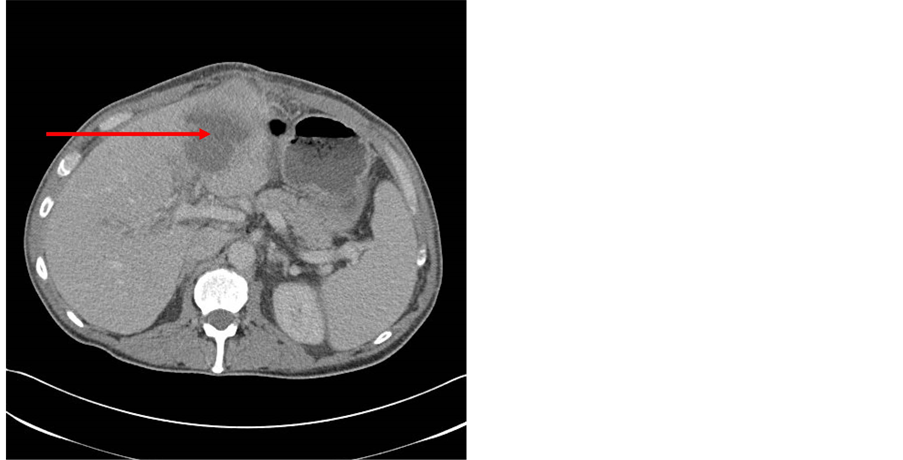

The workup for hypercoagulable state showed elevated Factor 8, which was thought the cause for the portal vein thrombosis, and he was started on Coumadin. While on Coumadin, he started having hematuria. As part of the workup for hematuria, a CT scan showed a large lobulated cystic structure within the lateral segment of the left lobe of the liver measuring 4.8 × 4.6 × 4.7 cm with a rim of surrounding edema in the left lobe, suggestive of hepatic abscess (Figure 1(a)). Thickening of the sigmoid colon wall and urinary bladder thickening adjacent to the inflamed sigmoid colon was also demonstrated, as well as a lobular collection filled with stool, air, and fluid along the posterior margin of the sigmoid colon. This was thought to be a large inflamed diverticulum (Figure 1(a)). The CT scan also showed air in the antidependent portion of the urinary bladder, suggestive of a fistula between the urinary bladder and sigmoid colon, suspicious for cancer of the sigmoid colon eroding into the urinary bladder, causing the fistula. For these reasons, the patient was admitted to the hospital.

Figure 1. (a) Showing liver abscess (arrow) Abdominal/pelvis region computed tomography scan image showing large lobulated cystic structure within the lateral segment of the left lobe of the liver measuring 4.8 × 4.6 × 4.7 cm with a rim of surrounding edema in the left lobe, suggestive of hepatic abscess, and (b) Showing sigmoid diverticulitis (arrow). Thickening of the sigmoid colon wall and urinary bladder thickening adjacent to the inflamed sigmoid colon was also demonstrated, as well as a lobular collection filled with stool, air, and fluid along the posterior margin of the sigmoid colon. This was thought to be a large inflamed diverticulum.